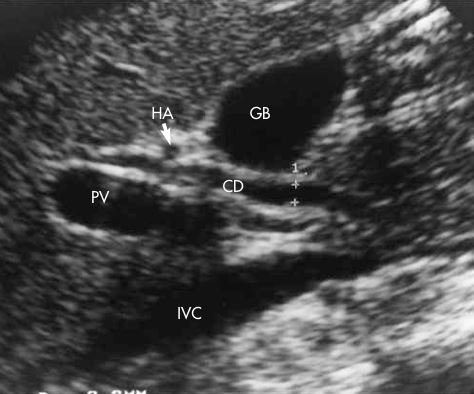

1. Portal Vein

2. Common Bile Duct

3. Gallbladder

arrow: HA

Common Bile Duct doesn’t catch COLOR

On this sagittal image, the hepatic artery (HA) is shown anterior to the common duct (CD)